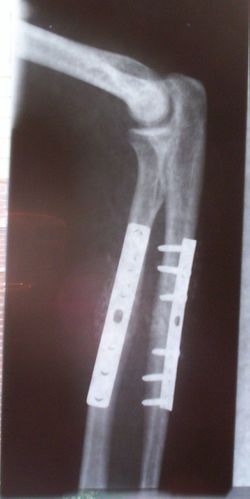

تقويم العظام

تساعد زراعة العظام في التخفيف من مشاكل عظام ومفاصل الجسم. يتم استخدامها لعلاج كسور العظام ، والتهاب المفاصل ، والجنف ، وتضيق العمود الفقري ، والألم المزمن . تشمل الأمثلة مجموعة متنوعة من المسامير والقضبان والبراغي والألواح المستخدمة لتثبيت العظام المكسورة أثناء الشفاء..[1][2][3]